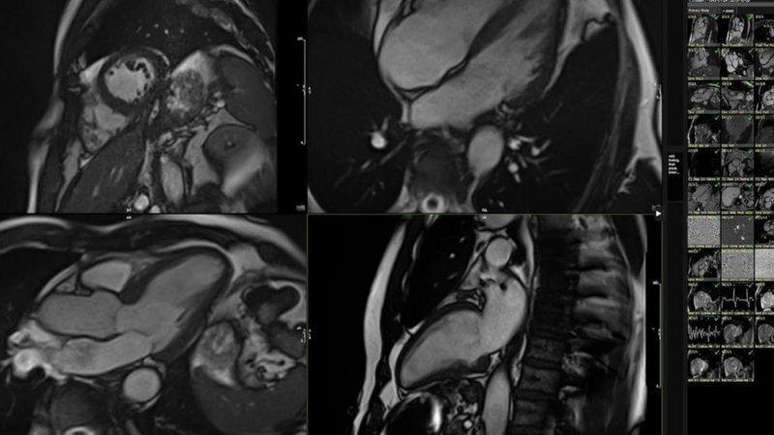

Comecei com uma ressonância magnética, feita após praticar um pouco de exercício leve.

Fizemos, entre outras coisas, uma ressonância magnética (MRI) do meu coração, logo após eu praticar um pouco de exercício.

O sistema analisou centenas de pequenos detalhes na animação em 3D da minha ressonância magnética e os comparou aos de 5 mil outras pessoas, de diferentes faixas etárias, todas com hábitos saudáveis.